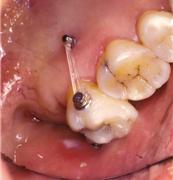

ºÎÁ¤±³ÇÕÀÌ Æ¯Á¤ ºÎÀ§¿¡ ±¹ÇѵǾî ÀÖ´Â °æ¿ì ƯÁ¤ Ä¡¾Æ¿¡¸¸ ÀåÄ¡¸¦ ºÎÂøÇÏ¿© ±³Á¤ ÇÏ´Â °æ¿ìµµ ÀÖ½À´Ï´Ù. Ʋ¾îÁ®ÀÖ´Â ¾Õ´Ï¸¸ ºÎºÐÀûÀ¸·Î °í¸£°Ô ¹è¿Çϰųª(±×¸²3) º¸Ã¶(ÀÓÇöõÆ®)À» À§ÇØ ¾²·¯Áø ¾î±Ý´Ï¸¦ ¹Ù·Î ¼¼¿ì´Â °æ¿ì(±×¸²4), »ó½ÇµÈ ´ëÇÕÄ¡ ¶§¹®¿¡ Á¤ÃâµÈ ¾î±Ý´Ï¸¦ ¾ÐÇϽÃŰ´Â Ä¡·á°¡ ´ëÇ¥ÀûÀÎ °æ¿ìÀÔ´Ï´Ù(±×¸²5). Áõ·ÊÀÇ ³À̵µ³ª ¹è¿»óÅ¿¡ µû¶ó Åë»ó 6°³¿ù ³»¿ÜÀÇ ±â°£ÀÌ ÇÊ¿äÇÕ´Ï´Ù.

| | ±×¸²4 |